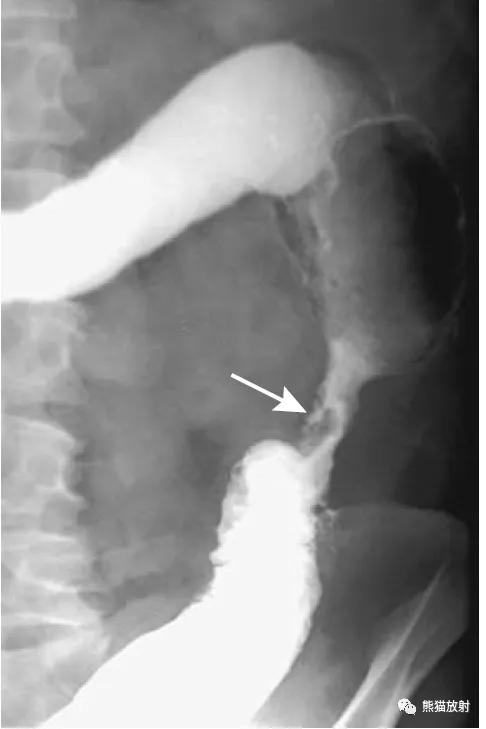

乙状结肠扭转。消化道造影侧视图可见乙状结肠局部走行扭曲(箭头)。